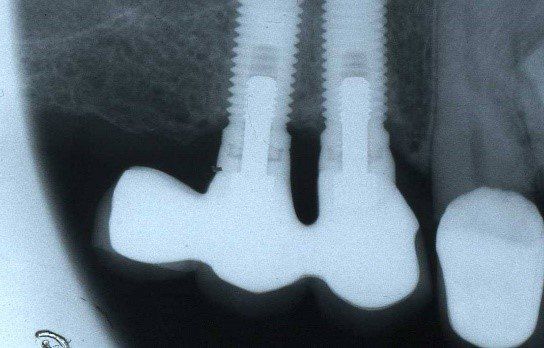

L'implantologia diventa quindi in questo ambito riabilitativo l'alternativa per eccellenza, in quanto permette il ripristino totale della funzione masticatoria con denti fissi. Tale protesi completa con impianti, è conosciuta come "Toronto Branemark Bridge" e prevede secondo il protocollo svedese originale, l'inserimento di un numero adeguato di impianti nelle arcate ed in posizioni idonee tali da sostenere meccanicamente la successiva protesi fissa ed il relativo carico masticatorio (almeno 6 nell’arcata superiore e 5 nell'inferiore). Relativamente al numero di impianti che sono necessari per soddisfare le condizioni meccaniche utili ad applicare su di essi una protesi fissa, negli ultimi anni è venuta a mancare la consueta chiarezza. Come detto poco sopra il protocollo svedese originale recita testualmente:

nell’arcata superiore “almeno sei impianti nell’area della premaxilla, ovvero l’area ossea compresa tra i seni mascellari da entrambi i lati”

nell’arcata inferiore “cinque impianti nella regione del mento, entro i limiti anatomici determinati dal nervo mentoniero”.